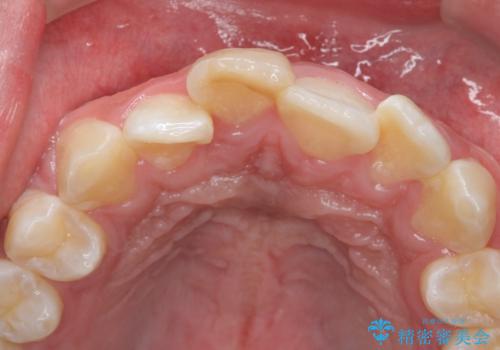

変色した前歯 根の治療とセラミックで白い歯に

- 前歯の変色を主訴に来院。

神経が死んでいたため、神経の治療を行いました。

また、全体的に歯石がついており、歯ぐきから出血しやすい状態であったため、TBI(歯磨き練習)を行い、歯茎の炎症をしっかり収めてから治療しました。

今後矯正治療をするかもしれない(未定)とのことでした。

その際、支障がでないように、患者様と相談し、他の歯を削って並びを整えるようなことはせず、前歯の角度はそれなりにそろえる形にしました。

神経が死んでしまった歯は時間がたつと変色してきてしまいます、セラミックでかぶせると色を改善することが可能です。